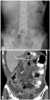

A gastroenterostomy is the surgical creation of a connection between the stomach and the jejunum. The operation can sometimes be performed at the same time as a partial gastrectomy (the removal of part of the stomach). [Source: Wikipedia ]